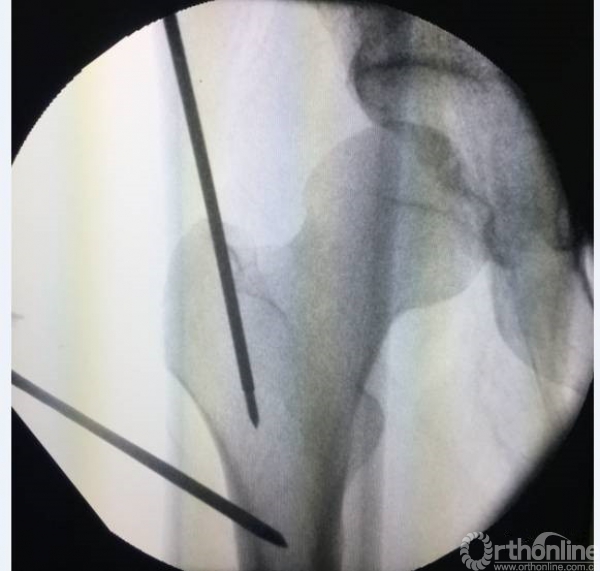

屈髋屈膝牵引入钉可以有效放松股骨近端的肌肉(髂腰肌、臀中肌),从而可以更好的进行骨折复位。尤其是粗隆下骨折

但进钉点不太适合选用梨庄窝进针,同时透视角度也需要进行微调。

同时可以对于近端复位不良时,可以采用顶棒纠正前后旋转,克氏针纠正内外旋转。